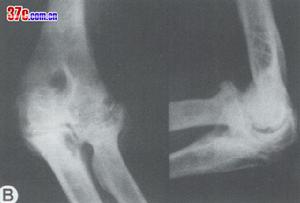

![]() | ![]() |

| 鐮狀細胞性貧血肘關節改變1 | 鐮狀細胞性貧血肘關節改變2 |